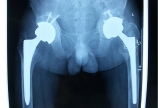

【髋关节】双侧全髋关节置换术后假体松动—同期翻修 VS分期翻修?

病情概述: 患者王某某,37岁,男性,工人,强直性脊柱炎20年,双侧全髋关节置换术后10年,双髋疼痛3年。术前查体左下肢较对侧短缩1cm左髋关节外旋15°、内旋6°,明显受限左髋关节外展27°、内收30°左髋关节屈曲28°、后伸19°,显著受限右髋关节外旋8°、内旋7°… [详情]